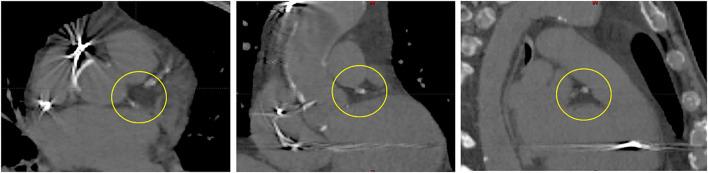

Radiotherapy planning CT series include scans at expiration and inspiration breath hold, and three free-breathing scans. All secondary series are triple registered to the primary CT: 6D/spine + 3D translation/marker + 3D translation/target surrogate-a heterogeneous structure around the left main coronary artery. The 3D translation difference between the last two registrations reflects the deformation between the marker and the target (surrogate) for the respective respiratory phase. Maximum translation differences in each direction form an anisotropic geometry deformation margin (GDM) to expand the initial single-phase clinical target volume (CTV) to create an internal target volume (ITV) in the dynamic coordinates of the marker. Alternative GDM-based target volumes were created for seven recent STAR patients and compared to the original treated planning target volumes (PTVs) as well as to analogical volumes created using deformable image registration (DIR) by MIM and Velocity software. Intra- and inter-observer variabilities of the triple registration process were tested as components of the final ITV to PTV margin.

A margin of 2 mm has been found to cover the image registration observer variability. GDM-based target volumes are larger and shifted toward the inspiration phase relative to the original clinical volumes based on a 3-mm isotropic margin without deformation consideration. GDM-based targets are similar (mean DICE similarity coefficient range 0.80-0.87) to their equivalents based on the DIR of the primary target volume delineated by dedicated software.